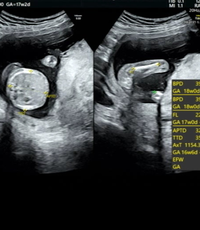

Amiさんの妊娠17週目のエコー写真 推定体重は3773g! 骨盤に入らず緊急帝王切開になった長女の成長をエコー写真で振り返る 右側のエコー写真には、お尻と脚が2本写っています。 このエコー検査から「性別は女の子かもしれない」と主治医の先生から言わ 妊娠18週|赤ちゃんの胎動や性別エコーの様子は?体重増加に注意 妊娠5ヶ月|体重増加や胎動、ママのお腹や胎児の大きさは? 出典:wwwamazoncojp みんなの妊娠18週目のエコー写真をご紹介します。 18週0日(18w0d・女の子)|surfrie さん(38歳) エコー写真撮影時のエピソード: なぜか、毎回17週 エコー 性別 Dr林「性別は必ず判定できるとは限らない」 最近では妊婦さんほぼ全員が、性別判定を希望します。 ただし、教えない方針の病院もあり、全部の医療機関が性別を教えるわけではありません。 また、技術的には男の子は妊娠14~15週、女の子は妊娠17~18週には判断できます

私の場合、1人目の男の子が17週で性別ほぼ確定となりました。 その際の記事はこちら。 エコー写真男の子の性別診断☆私の場合は17週で発覚! 男の子のエコー写真 男の子のシンボルが見えやすいエコー写真を集めてみました! ぜひ参考にしてみてくださいね☆ 17週の男の 妊娠24週ってどんな時期?! エコーで赤ちゃんの性別が確定できました♡女の子の場合でも断定できる!葉っぱマークや子宮が見えるって本当?? そしてツワリも終わって気をつけたいのが体重管理!! 妊娠中の体重増加の目安って?ツワリで減った場合は、どの時点の体重から考えるべ《男の子?女の子?》妊娠13週目のエコーで性別を見分ける方法 妊娠13週に入ると、子宮の大きさは小さなメロンほどになり、早い人だと胎動を感じることが出来ます。 12週を超えると流産のリスクもぐっと下がるので、安心して赤ちゃんのお迎えが出来て楽しい日々になりますよね。 安心